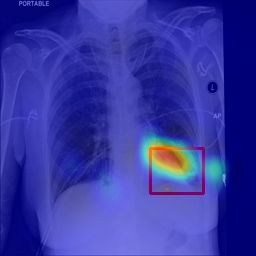

Deployments of artificial intelligence in medical diagnostics mandate not just accuracy and efficacy but also trust, emphasizing the need for explainability in machine decisions. The recent trend in automated medical image diagnostics leans towards the deployment of Transformer-based architectures, credited to their impressive capabilities. Since the self-attention feature of transformers contributes towards identifying crucial regions during the classification process, they enhance the trustability of the methods. However, the complex intricacies of these attention mechanisms may fall short of effectively pinpointing the regions of interest directly influencing AI decisions. Our research endeavors to innovate a unique attention block that underscores the correlation between 'regions' rather than 'pixels'. To address this challenge, we introduce an innovative system grounded in prototype learning, featuring an advanced self-attention mechanism that goes beyond conventional ad-hoc visual explanation techniques by offering comprehensible visual insights. A combined quantitative and qualitative methodological approach was used to demonstrate the effectiveness of the proposed method on the large-scale NIH chest X-ray dataset. Experimental results showed that our proposed method offers a promising direction for explainability, which can lead to the development of more trustable systems, which can facilitate easier and rapid adoption of such technology into routine clinics. The code is available at www.github.com/NUBagcilab/r2r_proto.